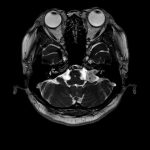

断層撮影

手術前2